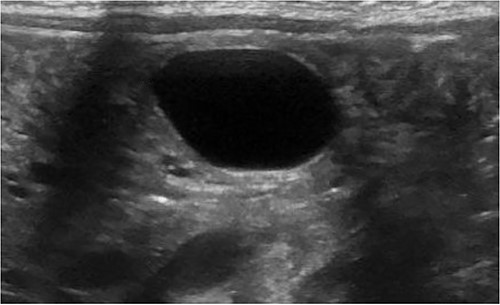

A 3.5 kg male was born via spontaneous vaginal delivery at 38 weeks. A chest radiograph demonstrated opacity at the medial right lung base (Fig. 1) consistent with the known congenital lung malformation. An abdominal ultrasound demonstrated a simple cyst with a gut signature consistent with an enteric duplication cyst (Fig. 2).

An additional abdominal ultrasound was obtained at two months of age, which redemonstrated a growing hypoechoic cystic structure with the persistence of a gut signature. A chest CT scan was obtained per institutional protocol for congenital lung malformations at ten weeks of age, which demonstrated an ill-defined area containing small cysts in the medial right lower lobe without systemic vascular supply or bronchial distribution consistent with a CPAM. Excision of both lesions was recommended, which the parents agreed to. The decision was made to proceed with laparoscopic duplication cyst resection followed by thoracoscopic right lower lobectomy 6 weeks later.